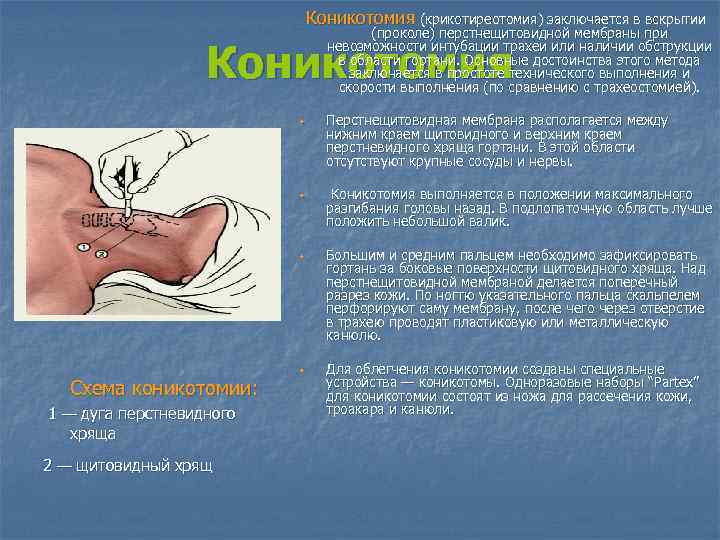

Коникотомия (крикотиреотомия) заключается в вскрытии (проколе) перстнещитовидной мембраны при невозможности интубации трахеи или наличии обструкции в области гортани. Основные достоинства этого метода заключается в простоте технического выполнения и скорости выполнения (по сравнению с трахеостомией). Коникотомия w w w Схема коникотомии: 1 — дуга перстневидного хряща 2 — щитовидный хрящ w Перстнещитовидная мембрана располагается между нижним краем щитовидного и верхним краем перстневидного хряща гортани. В этой области отсутствуют крупные сосуды и нервы. Коникотомия выполняется в положении максимального разгибания головы назад. В подлопаточную область лучше положить небольшой валик. Большим и средним пальцем необходимо зафиксировать гортань за боковые поверхности щитовидного хряща. Над перстнещитовидной мембраной делается поперечный разрез кожи. По ногтю указательного пальца скальпелем перфорируют саму мембрану, после чего через отверстие в трахею проводят пластиковую или металлическую канюлю. Для облегчения коникотомии созданы специальные устройства — коникотомы. Одноразовые наборы “Partex” для коникотомии состоят из ножа для рассечения кожи, троакара и канюли.